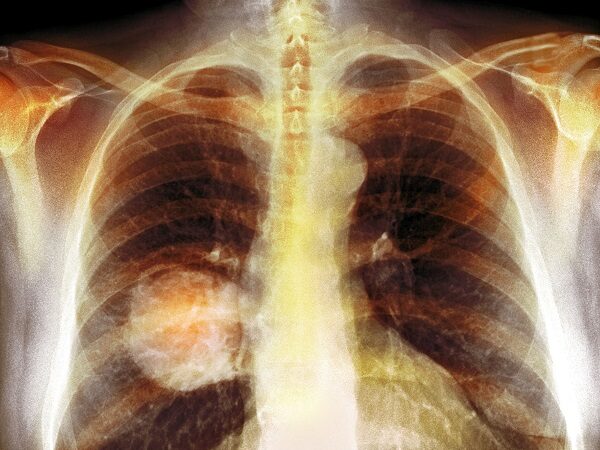

سرطان ریه چیست؟ (همه چیز در مورد سرطان ریه)

سرطان ریه چیست؟

منشأ سرطان ریه در بافت ریهها و سلولهای پوششی مجاری تنفسی (نایژهها) است. این سلولها در زیر میکروسکوپ ظاهری مشابه با سلولهای سرطانی ریه دارند، اما تغییراتی که در فرآیند سرطانی شدن رخ میدهد را ندارند.

ترکیبی از مطالعات تصویری، ازجمله اسکنهای CT، MRI و PET ممکن است برای تشخیص سرطان ریه مورد استفاده قرار گیرد. علاوه بر این، بیوپسی (نمونهبرداری از بافت) ریه نیز معمولاً برای تعیین نوع سرطان ریه لازم است.